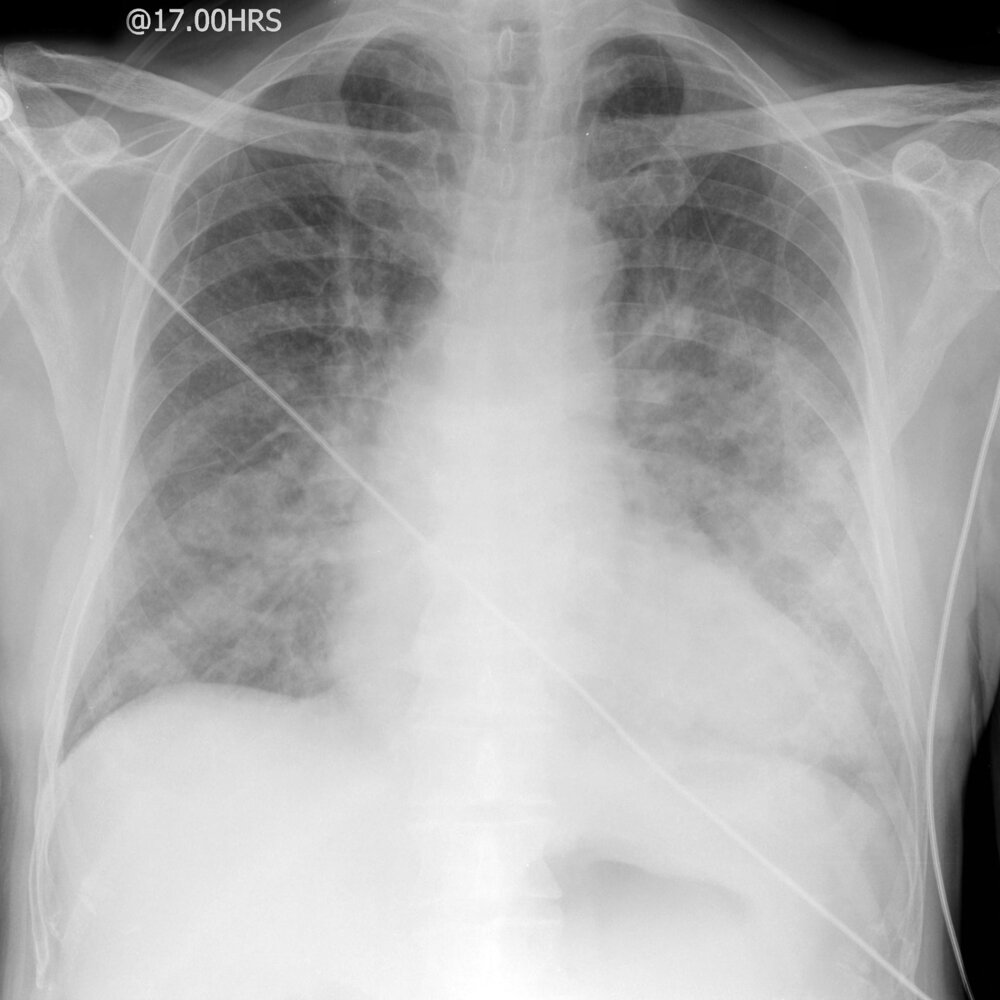

Chest x-ray [7][20]

-

Chest x-ray findings in cardiogenic pulmonary edema

- Enlarged heart shadow due to cardiomegaly and/or pericardial effusion [21]

- Kerley B lines (also known as septal lines)

- Prominent pulmonary vessels and perihilar alveolar edema (the hilar shadow has a butterfly or “bat wing” appearance)

- Basilar interstitialedema

- Bilateral pleural effusions [22]

- Cephalization: increased prominence of pulmonary vessels in the upper lobes of the lungs due to venous congestion [23]

- Peribronchial cuffing

ABCDE: Alveolar edema (bat wings), Kerley B lines (interstitial edema), Cardiomegaly, Dilated prominent pulmonary vessels, and Effusions